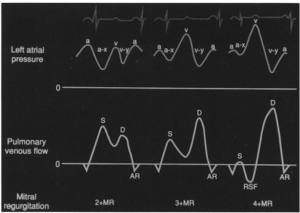

さて、僧帽弁逆流症例において、その波形がどうなるかに関しては次の図をご覧ください。

(僧帽弁逆流重症度によるPV波形の変化: 文献[6]より引用)

(僧帽弁逆流重症度によるPV波形の変化: 文献[6]より引用)

注目すべきはS波です(MRが収縮期なんだから当たり前か)。MRが重症化するにつれ、S>D→S<D→reverse Sの出現と波形が変化していきます。この変化が今回の論文のキモです。